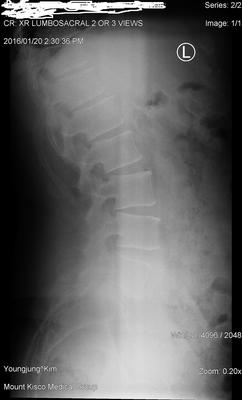

And finally, I must add that due to a sport injury which incurred when I was about 14 years old, I twisted my left foot. As a result my left foot is almost flat and perhaps my left leg is a bit shorter. I never addressed that injury. So my feet are not symmetrical now. This could explain the abnormal curve you see in the x-ray from my spine. I can provide much more details but allow me to await your response first.

Let's start with the x-rays. There are three significant findings. Firstly on the lateral lumbar (is an extension view?) there a sharp posterior angulation of L2 on L3 which is indeed where the superior cluneal nerves emanate from.

Your foot injury, particularly if it's left you with a short leg, or a slight limp may be very significant. Have someone stand behind you, place the hands on the iliac crests, and see if one side is definitely lower than the other. And when you bend forwards, do you develop an obviously scoliosis? A simple inexpensive heel lift may be a big part of the solution.